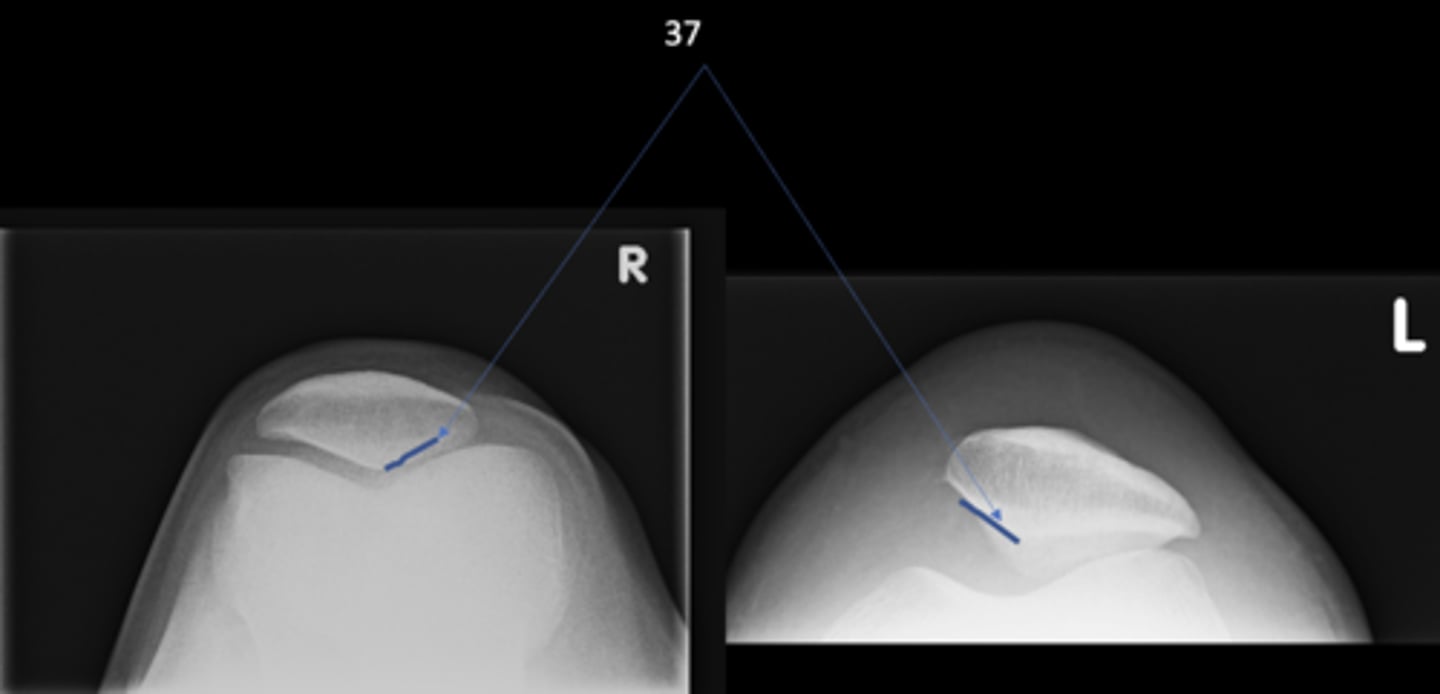

14

AP hip

View on left?

<p>View on left?</p>

23

New cards

Frog-leg hip

View on right?

<p>View on right?</p>

- Medial margin of femoral head

- Lateral border of teardrop

Kohler's teardrop distance landmarks

<p>Kohler's teardrop distance landmarks</p>

6-11 mm

Normal Kohler's teardrop distance measurement

<p>Normal Kohler's teardrop distance measurement</p>

39

2 mm

The normal Kohler's teardrop distance is 6-11 mm, and there should be no greater than a _____ difference when comparing to the contralateral side

<p>The normal Kohler's teardrop distance is 6-11 mm, and there should be no greater than a _____ difference when comparing to the contralateral side</p>